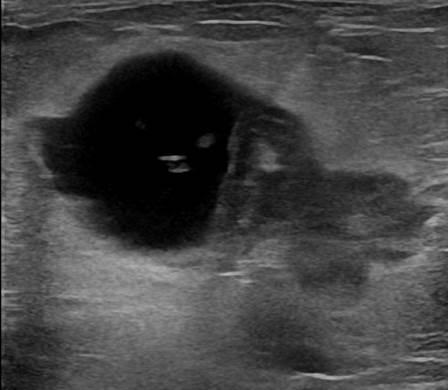

Ung thư vú

» Thông tin: Nữ giới – 55 tuổi.

» Lâm sàng: Khối tuyến vú.